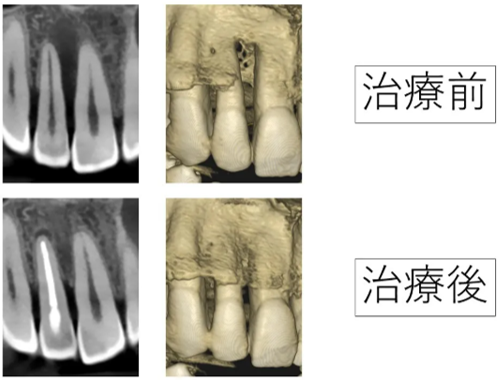

残す事が難しい根の病気を顕微鏡(マイクロスコープ)を用いて治療した症例